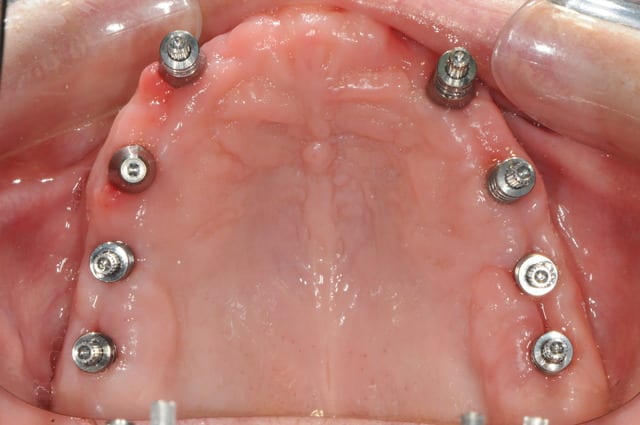

23/06/2010 à 01h44

l'heure des comptes va bientôt sonner...

je débute la prothèse définitive, ai je raison de m'y prendre si tôt ?

vos avis ...

nous ne sommes qu'à deux mois et demi.

pour ce qui est du PE, je me suis trompé grave sur le nombre de transfert d'empreinte pick up à commander, je l'ai donc fait avec un pop-in